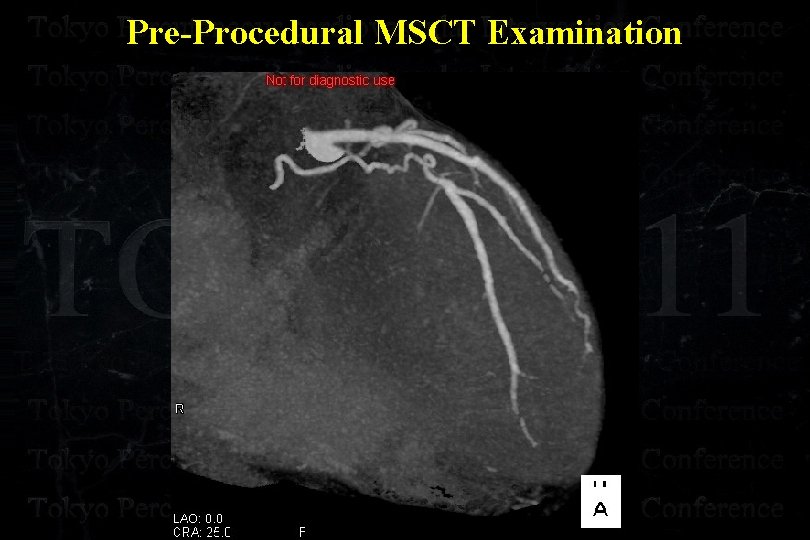

Pre-Procedural MDCT Examination

Pre-Procedural MSCT Examination

Pre-Procedural MSCT Examination

Pre-Procedural MSCT Examination